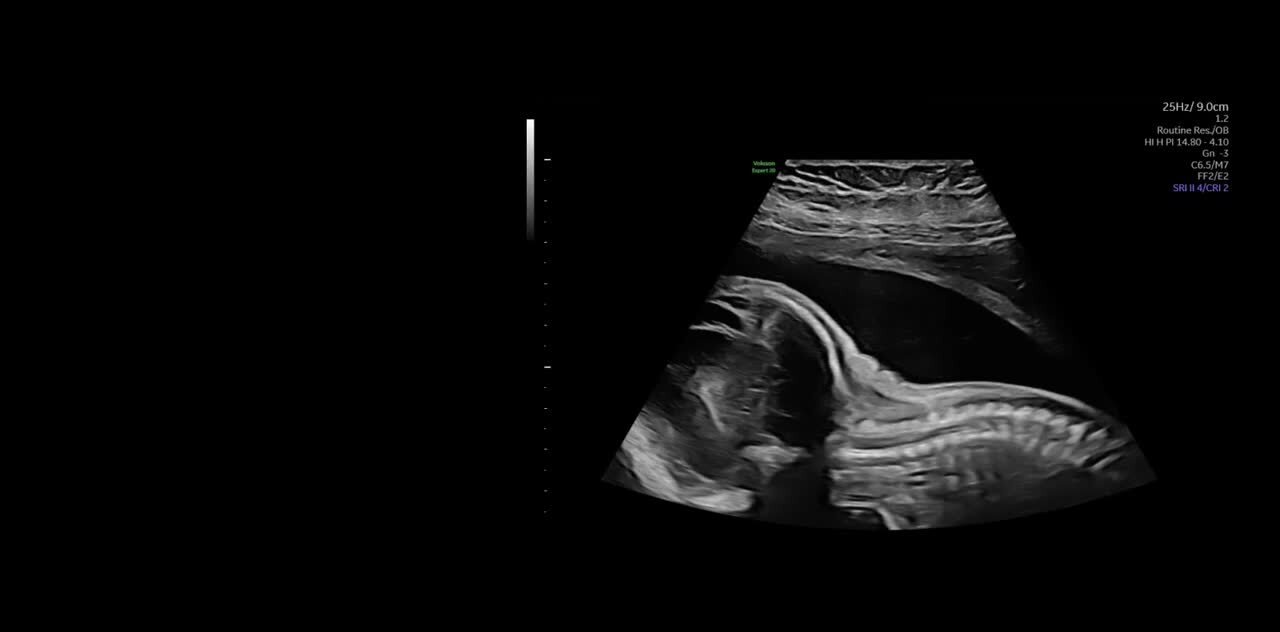

Voluson Expert 22 построен на совершенно новой высококачественной платформе Lyric Architecture, которая использует формирование луча на основе графики. Voluson Expert 22 создан для визуализации, которая сочетает в себе исключительное качество изображения, превосходные технологии объемного ультразвука и возможности искусственного интеллекта.

- Генерирует новые уровни проникновения, разрешения и частоты кадров для легкого выявления тонкой анатомии в 2D/3D/4D

Клиническое применение: Исследования сердца у детей и новорожденных, педиатрия, малые органы. - eM6C G3 — Объемный мультичастотный электронный матричный конвексный датчик 4D, с диапазоном частот 2-6 МГц.

Клиническое применение: Абдоминальные и акушерско-гинекологические исследования" - RM7C — Объемный конвексный мультичастотный матричный монокристальный датчик 4D, с диапазоном частот 2-8 МГц. Уменьшенные эргономичные габариты.